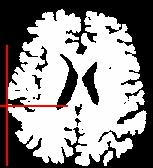

An illustration of the process at the level of a slice:

The grey level image is thresholded first in order to get a binary object (white on black background). During a second stage, an erosion process is simulated in order to trim the object until a given thickness. This erosion fathers several disconnected pieces. The largest one is selected as a seed of the brain. A dilation process makes the seed growth in order to recover the actual brain shape.